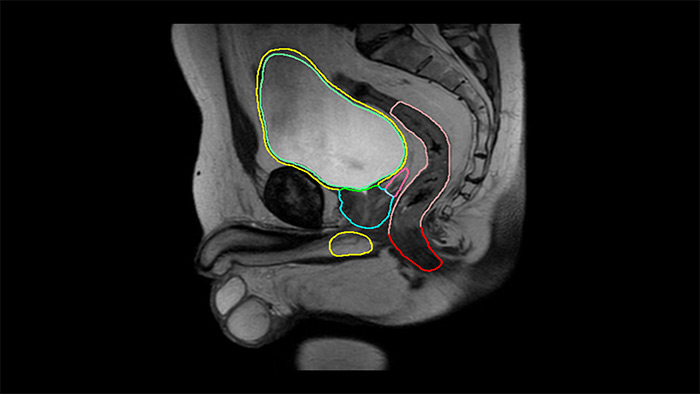

Sistemas de imágenes por resonancia magnética

Una nueva cartera de soluciones de Resonancia Magnética que ofrece velocidad, comodidad y seguridad, con el fin de mejorar la atención al paciente.